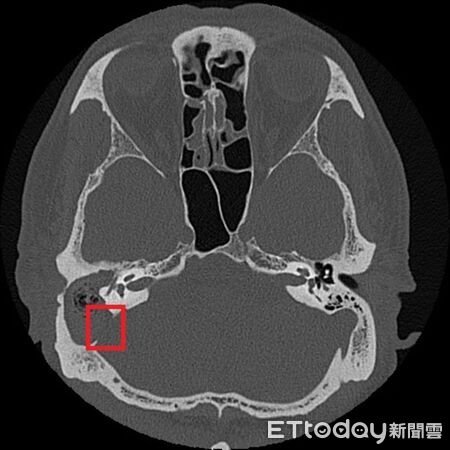

▲從張先生的影像可看到與後顱窩相隔的骨板遭膽脂瘤侵蝕(紅框處)。(圖/台北慈院提供)

鄭靜雯表示,經顳骨電腦斷層檢查後,確認為慢性中耳炎併發膽脂瘤,且已侵蝕顱底骨質,需立即住院,並以抗生素控制感染,待發炎情形穩定再安排手術,先打開乳突骨,完整清除病變組織,並同步進行鼓室重建、外耳道成形及顱底缺損修補,術後恢復良好。